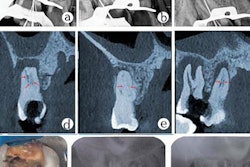

A CT scan (coronal section) shows the patient's right lateral orbit subperiosteal abscess, identified by a black arrow, and right maxillary sinusitis. All images courtesy of Houle et al. Licensed under CC BY 4.0.It is rare for an odontogenic infection to cause an orbital abscess, but when it does it can have severe effects, including a cavernous sinus thrombosis that can lead to death. Timely recognition and management of this condition can prevent serious complications.

A panoramic radiograph shows the restoration of tooth #3 with periapical radiolucency and right maxillary sinusitis.In addition, a CT scan taken at the outside hospital was reviewed by medical center clinicians. They identified a subperiosteal abscess at the right lateral orbit. The right canine space abscess came from the buccal roots of tooth #3. Also, the scan showed that fluid collected at the right canine space superiorly and posteriorly to the right lateral orbit, and right maxillary sinusitis was present.